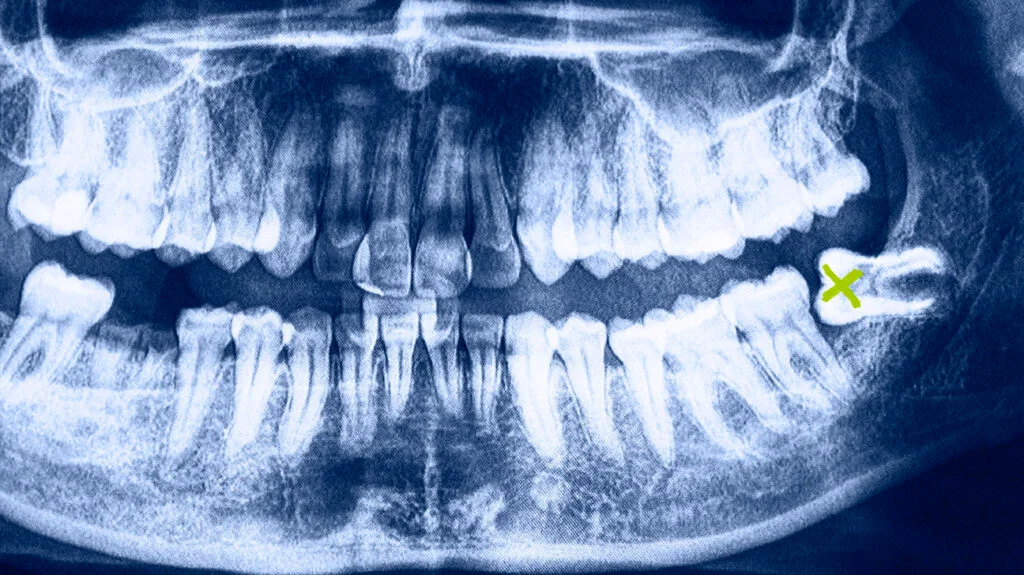

Wisdom tooth pain often strikes without warning, bringing swelling, jaw stiffness, and intense discomfort. At Colac Smiles, we regularly help patients from Winchelsea, Beeac, Cororooke, and Barongarook manage painful wisdom teeth effectively and avoid complications. Here’s what causes wisdom tooth pain, how to get relief, and when to seek dental treatment.

Wisdom teeth, also called third molars, usually erupt between ages 17 and 25. They are the last teeth to emerge and often lack enough space to come in properly. As a result, they can cause:

Impaction – Tooth is trapped in the jawbone or gums, leading to pressure, swelling, or infection

To avoid these complications, your dentist may recommend wisdom tooth removal, especially if the tooth is partially erupted, impacted, or repeatedly infected.

Wisdom tooth extraction can be simple or surgical, depending on the tooth’s position. At Colac Smiles, we provide:

Digital imaging and diagnosis